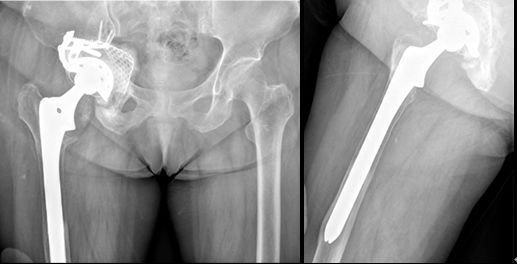

70岁女性,THA术后1年松动,翻修术后仍有疼痛,生活不能自理

第二次翻修取出的臼、柄、骨水泥块,肉芽肿组织

第三次翻修术后3年,髋关节无痛,功能可,生活可以自理